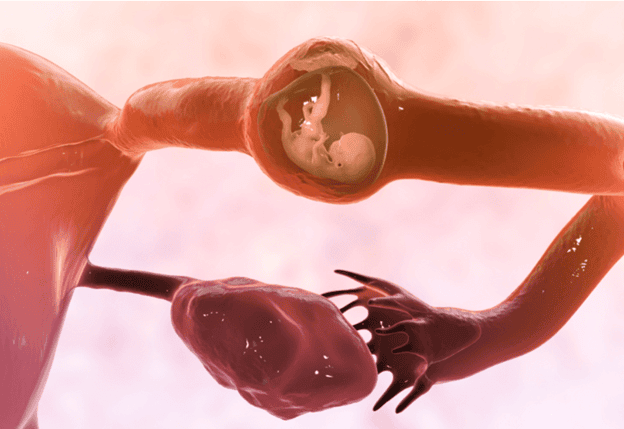

بارداری خارج از رحم زمانی اتفاق می افتد که یک تخمک بارور شده در خارج از رحم رشد کند. تقریباً همه حاملگی های خارج از رحم یعنی بیش از 90٪ در لوله فالوپ یا همان لوله رحمی رخ می دهد. همانطور که بارداری رشد می کند، می تواند باعث ترکیدن لوله (پارگی) شود. پارگی می تواند باعث خونریزی داخلی شدید شود و این شرایط یک اورژانس تهدید کننده حیات است که نیاز به مداخله جراحی فوری دارد.

محلهای مختلف حاملگی خارج از رحم: